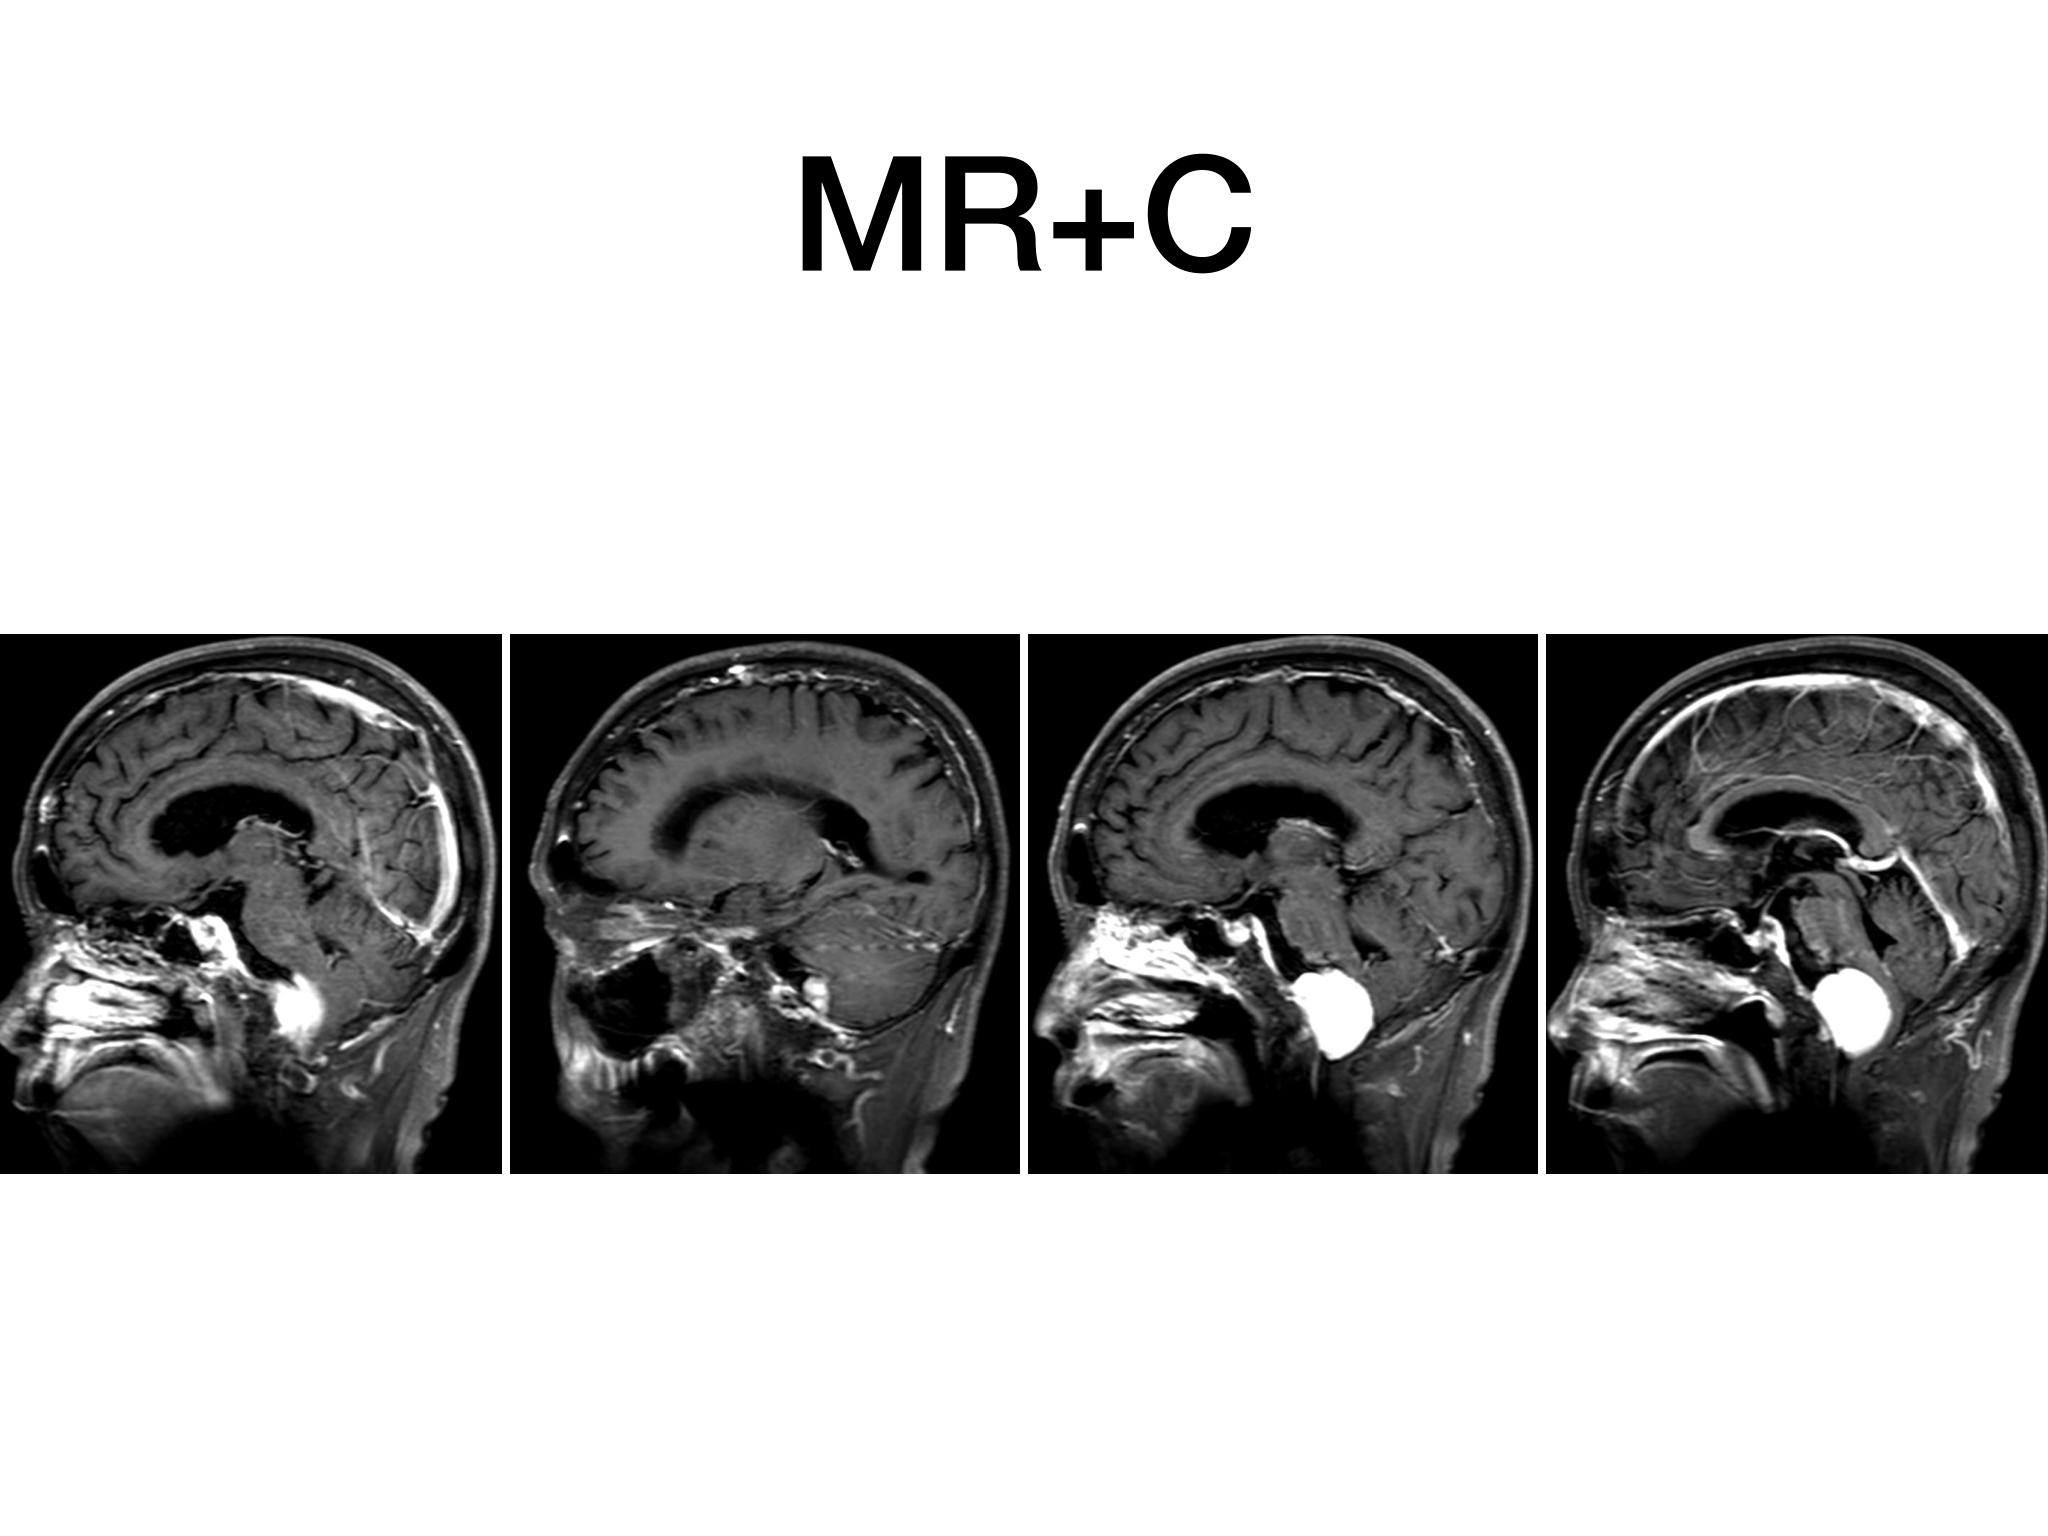

汇报一例后颅底肿瘤手术。为枕骨大孔巨大腹侧型脑膜瘤,该患者高龄,同时合并肺Ca,术前2周急性加重,枕骨大孔疝前期表现,术前已有延髓压迫及后组颅神经麻痹表现。经详细评估后采用远外侧经髁窝入路,最大化显露,重点保护延髓、后组颅神经,尽可能“零骚扰”。术中肿瘤质地韧,血供一般,与肿瘤上极与后组颅神经黏连紧密,最终99%切除,残留约1%,术后顺利康复出院,无新发症状,为后续进行肺部病变化疗创造有利条件。

远外侧经髁窝入路切除大型枕骨大孔腹侧脑膜瘤